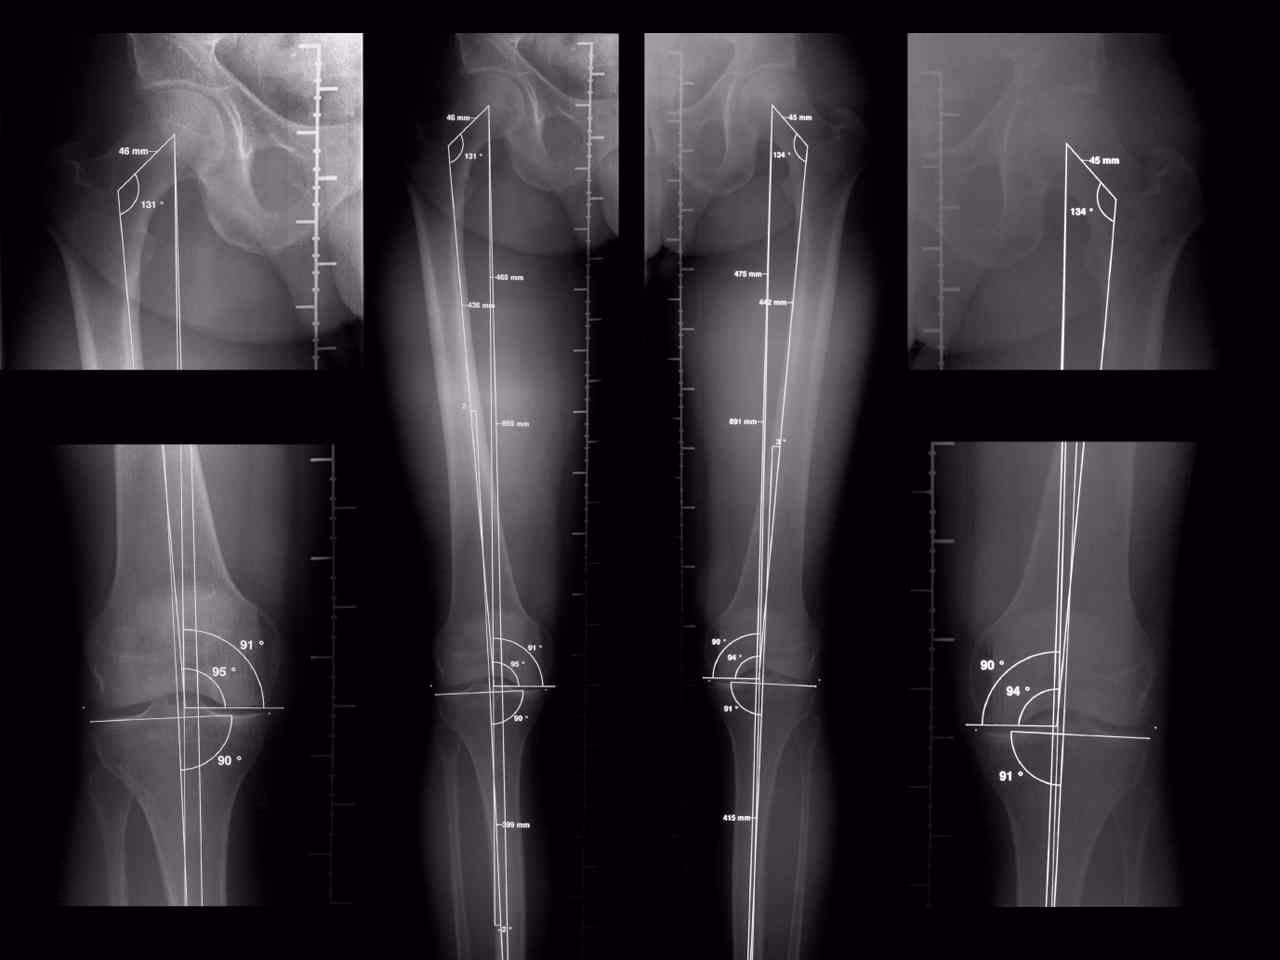

La telemetría de miembros inferiores, o telerradiografía, es un tipo específico de radiografía que se caracteriza por su amplio campo de visión. A diferencia de las radiografías estándar que suelen enfocarse en una articulación o segmento óseo particular, la telemetría captura una imagen completa que abarca desde las articulaciones de los tobillos hasta las caderas. Esta amplitud es esencial para evaluar la relación entre diferentes partes de la pierna y su alineación global.

La particularidad de esta radiografía es que se realiza con el paciente en posición de pie. Estar de pie es fundamental porque permite evaluar la alineación y la longitud de las piernas bajo la carga natural del peso corporal, que es la condición en la que las extremidades trabajan la mayor parte del tiempo. Esta posición revela cómo se distribuyen las fuerzas a través de las articulaciones y si existen desviaciones o discrepancias que no serían evidentes en una radiografía tomada en otra posición.

El equipo de radiografía captura una imagen panorámica de las extremidades inferiores. Debido a la longitud que debe cubrir la imagen, algunos equipos modernos realizan varias tomas secuenciales que luego son unidas digitalmente para crear una única imagen larga y continua. Este proceso asegura que se capture toda la longitud de los huesos largos (fémur y tibia) y su relación con las articulaciones principales (cadera, rodilla y tobillo).

2. Evaluar la alineación angular: La telemetría permite medir los ángulos que forman los huesos largos entre sí y con respecto a los ejes mecánicos y anatómicos. Esto es crucial para identificar desviaciones como el valgo (piernas en X) o el varo (piernas arqueadas). Estas angulaciones anormales pueden aumentar significativamente la carga sobre ciertas áreas de las articulaciones, llevando a su desgaste prematuro.